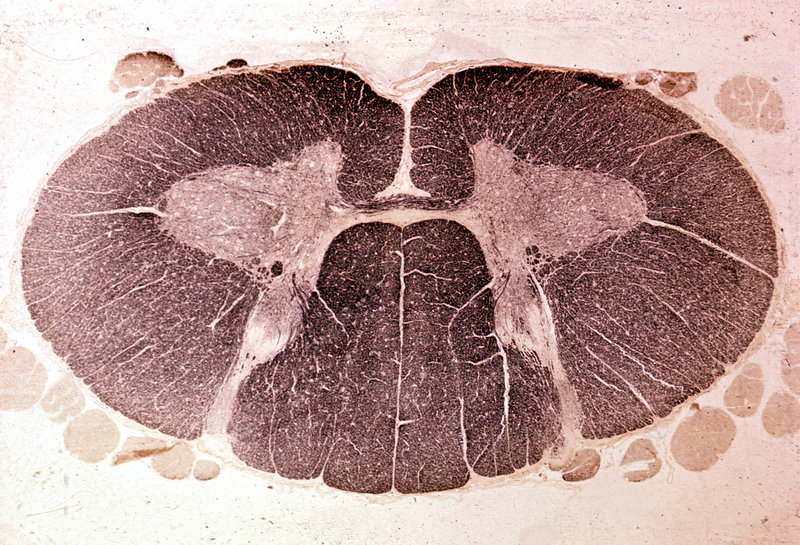

A human cervical spinal cord slice. Once you’ve read this post, you should be able to identify the major parts and tell which side is the front of the cord.

Welcome to day thirty-three in our series. For those of you who are just finding us, we have every one of these posts in our neuroanatomy category in reverse chronological order. Today we’re going to backtract (get it?) a little and go over something basic, but something we’ve skipped over to this point. We never really talked about the landmarks of a spinal cord slice. So today, we are going to take a detour and go over spinal cord features.